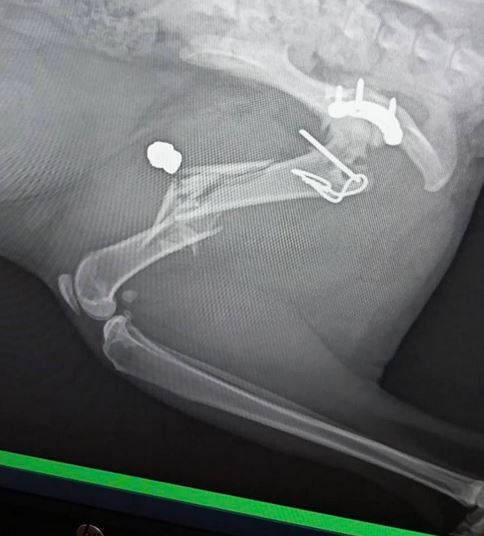

Дамата разгласява и фотоси на едно от потърпевшите животни, което е било простреляно в крайници. Сачмата раздробила крайници на четириногото, като се наложила ветеринарна помощ.

" Пресен случай на тази свирепост е котето Франки – простреляно, със счупено и раздробено от сачмата краче! Споделям тази информация с всички вас, с цел да сигнализирате, в случай че забележите лице, стрелящо от терасата за развлечение, и да се вземат нужните ограничения. Не би трябвало да разрешаваме такава свирепост да остане ненаказана! ", написа Анева.